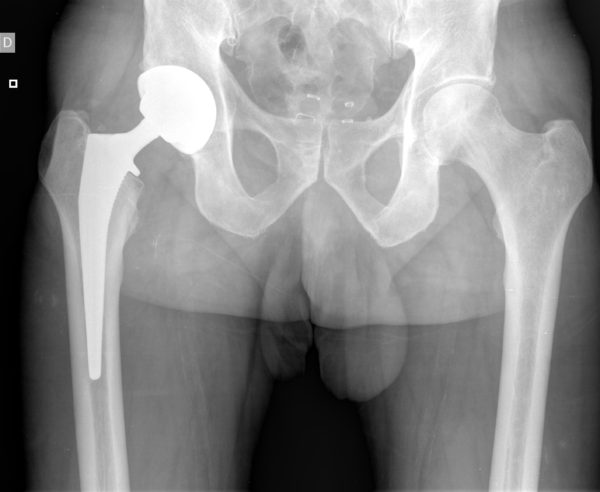

Radiographie prothèse de hanche

La chirurgie de la prothèse de hanche consiste à remplacer les surfaces articulaires endommagées par des implants adaptés. L’intervention est réalisée dans un cadre hospitalier, selon des protocoles chirurgicaux établis. Chaque prise en charge est individualisée.